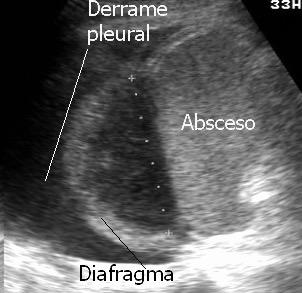

33. EMPIEMA PLEURAL. ULTRASONIDOS EN

34. EMPIEMA PLEURAL. SIGNOS EN TC.

Patrón ecográfico de empiema

Anecoico.....0%. (0 de 47)

Complejo no septado no hiperecoico... ……………..0% (0 de 36)

Complejo, no septado hiperecoico......100% (2/2)

Complejo septado …35% (11 de 31)

Ecogénico homogéneo .... 100% (2 de 2)

Wang T et al. Value of ultrasonography in determining the nature of pleural effusion. Analysis of 582 cases. Medicine 2022.

Chih-Yen Tu et al. Chest Ultrasound Study Pleural Effusions in Febrile Medical ICU. Chest 2004

Yang W,et al. Infectious pleural effusion status and treatment progress. J Thorac Dis. 2017;